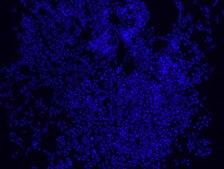

Eubacteria probe recognizes most bacteria as it is complementary to a portion

of 16S rRNA found in almost all bacteria.9,10

FISH technique was successfully used to identify different bacteria with the universal bacterial probe in various samples such as, pure culture (as described in the figure legends), blood cultures10,11, periapical tooth lesions12, saliva13, biofilms from voice prostheses14, subgingival biofilm15, aortic wall tissue16, buccal epithelial cells, pure culture and cell culture17, intestine tissue embedded in paraffin18, necrotizing fasciitis and pure culture19, colon sections embedded in paraffin20,21, cancer tissues22,23, environmental samples24 and gut of the medicinal leech25. The probe can also be used for combined technique of FISH and Flow cytometric analysis. 9,26,27

Probe for fluorescence in situ hybridization (FISH), recognizes Eubacteria cells.